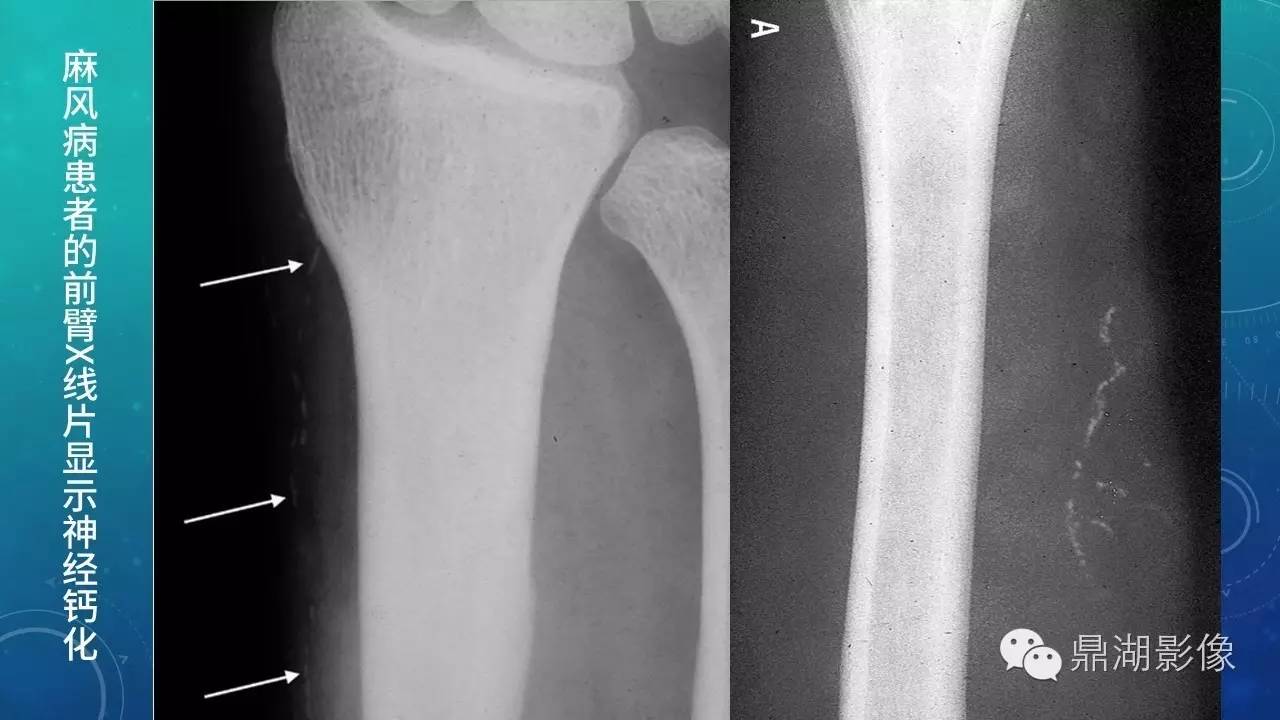

软组织钙化(的鉴别)